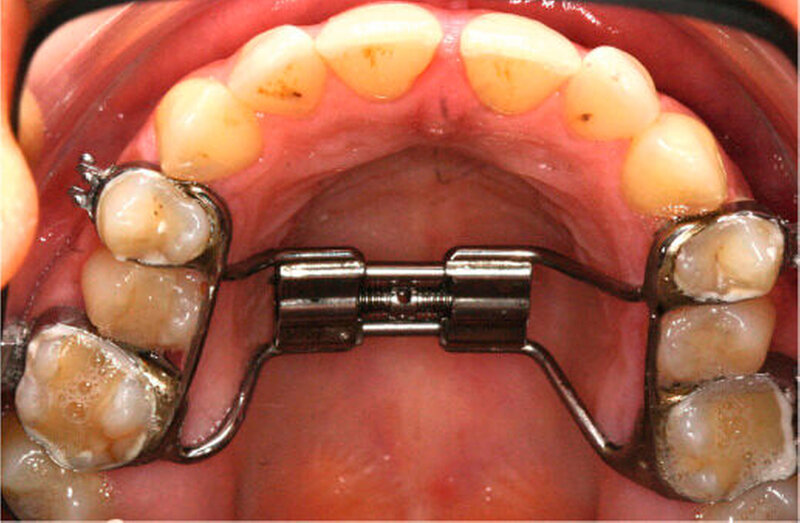

Anfangs wurde bei der Patientin eine transversale Expansion von etwa 5 mm mittels konventioneller GNE (Abbildung 3a) durchgeführt. Nach sechsmonatiger Retention durch Belassen der GNE-Apparatur konnte die individualisierte linguale Apparatur (Incognito, 3M Unitek, TOP-Service für Lingualtechnik GmbH, Bad Essen) eingesetzt werden (Abbildung 3b).